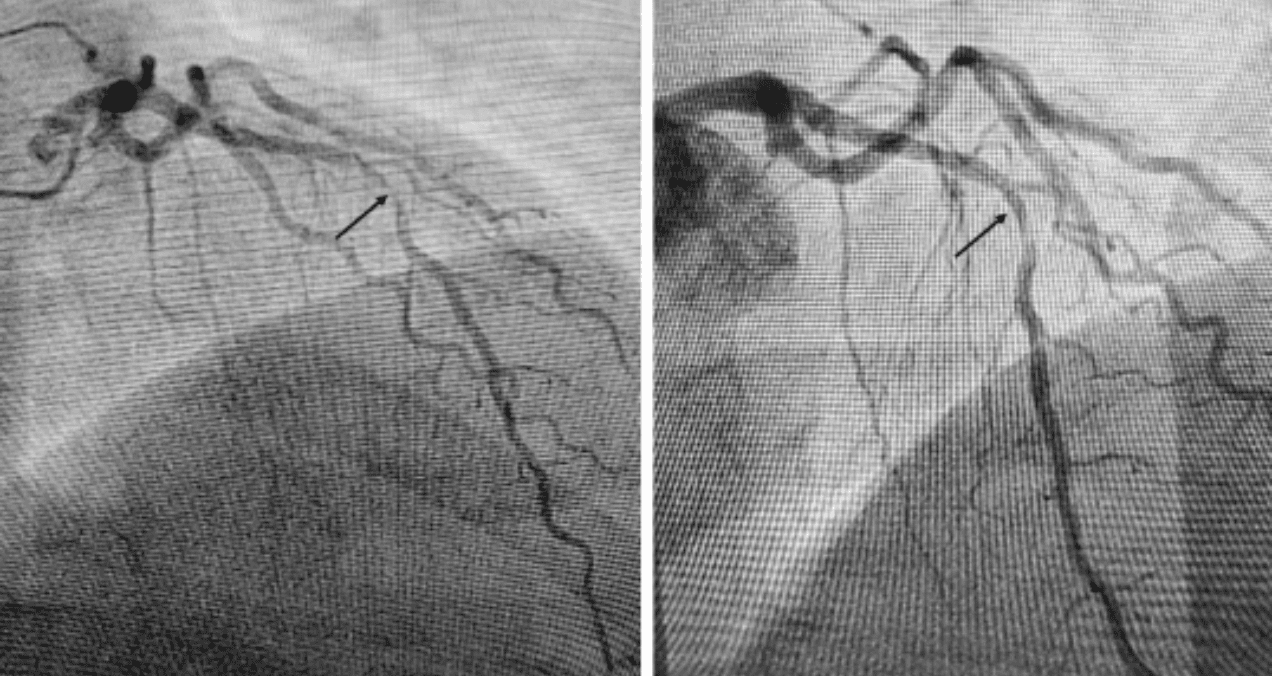

El paciente fue trasladado para cateterismo cardíaco urgente, donde se identificó una lesión crítica en la arteria descendente anterior (DAI), conocida coloquialmente como "la arteria asesina". Se realizó angioplastia con colocación de stent, logrando la revascularización exitosa del territorio afectado.

Durante el seguimiento, el paciente desarrolló trombosis del stent que requirió cirugía de revascularización coronaria (bypass) en 2023, tras lo cual evolucionó favorablemente sin necesidad de nuevas intervenciones.